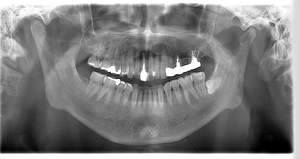

インプラント治療の症例3

レントゲン写真

- Befor

- After

口腔内写真

| 年齢 | 50代・男性 |

| 主訴 | 左下7番 |

| 治療内容 | 右下7番インプラント埋入 |

| 治療費 | 合計:572,000円 診断料:55,000円 埋入料:165,000円 サージカルガイド:55,000円 静脈内鎮静麻酔:77,000円 仮歯:55,000円 上部構造(フルジルコニア):165,000円 (2023年1月現在) |

| 治療期間 | 約8ヶ月 |

| 治療方針 | 骨が十分にあるため、骨造成をすることなく埋入した。かみ合わせが強いので、負荷がかからないよう、夜寝るときにマウスピースをつけるよう指示をした。 |

| 担当者所見 | 左下6番7番のインプラントは他院で埋入しており、右下7番は抜歯したままで、かみ合わせの歯が落ちてきてしまうのでインプラントを埋入しました。 |